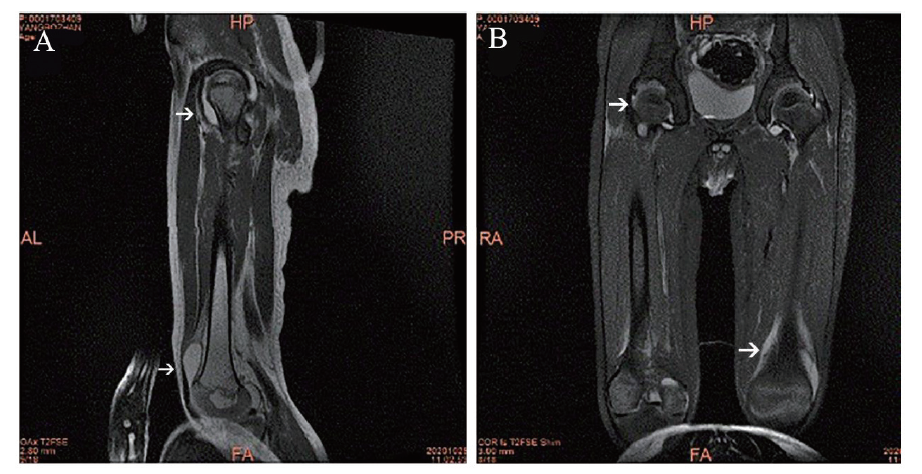

图1 例1丙种球蛋白非敏感型川崎病患儿髋、膝关节MRI

A:左侧臀大肌及左侧臀部皮下软组织显示异常炎症信号影;A、 B:双侧髋关腔长T1、长T2信号影,提示存在积液;C、D:膝关节腔及髌上囊长T1、长T2信号影,提示存在积液,右侧膝关节内、外侧半月板前后交叉韧带信号不均匀

例 1 患儿女,3岁,因发热和皮疹8 d于2020年3月31日入我科。起病以来患儿体温最高达40℃,全身出现散在皮疹、无瘙痒,偶有咳嗽,起病4 d后出现双下肢疼痛并呈进行性加重,不能独站及行走,不能握持。曾于当地诊所口服头孢克肟颗粒联合阿奇霉素治疗3 d,患儿仍持续发热,皮疹加重,遂转至当地县医院就诊,诊断为川崎病,停用抗生素,给予静脉滴注丙种球蛋白(2 g/kg)及口服阿司匹林[30 mg/(kg·d)],患儿仍反复发热,双手及双下肢疼痛加重。为进一步诊治入我科,入院体格检查:体温38.6℃,心率146次/分,神志清晰,精神差,急性病容,全身散在淡红色皮疹,压之褪色。颈部可触及多发肿大淋巴结。双侧上眼睑发红,双侧球结膜充血,未见分泌物。口唇皲裂、草莓舌、口腔及咽部黏膜弥漫性充血。心、肺、腹无异常。肛周潮红。四肢末梢硬肿、充血,指趾关节肿胀发红伴触痛,双侧髋关节、膝关节、踝关节均有压痛,未见肿胀。实验室检查:血红蛋白88 g/L,红细胞3.32×1012/L,白细胞18.17×109/L,血小板377×109/L。CRP > 200 mg/L,ESR 111 mm/h。白蛋白22 g/L。电解质、钙、镁和磷酸盐均正常。脑钠肽正常。IL-6 303.8 pg/ml(参考值范围 ≤5.4 pg/ml)。脑脊液有核细胞计数90×106/L(参考值范围 0 ~ 8×106/L)。抗O阴性。血液培养阴性。RF、抗核抗体谱均阴性。辅助检查:超声心动图显示冠状动脉左主干2.30 mm(Z值= 0.65)、右冠状动脉2.00 mm(Z值= 0.32),无冠状动脉损害。标准12导联体表心电图正常。MRI显示双侧髋关节腔、膝关节腔及髌上囊积液,右侧膝关节内、外侧半月板前后交叉韧带信号不均匀,左侧臀大肌及左侧臀部皮下软组织异常炎症信号(图1)。诊断为丙种球蛋白非敏感型川崎病合并严重关节炎、无菌性脑膜炎。再次给予患儿大剂量丙种球蛋白(2 g/kg),继续予口服阿司匹林[30 mg/(kg·d)],加用甘露醇降颅压。经上述治疗后患儿皮疹消退,但仍有持续低热,最高体温不超过38.5℃,下肢及手指疼痛不能缓解,遂予口服泼尼松[起始量2 mg/(kg·d)]治疗,用药2 d后患儿体温逐渐降至正常,双手及肢体疼痛减轻,阿司匹林循序减量为3 mg/(kg·d)。恢复期患儿出现了指趾末梢脱皮及双上眼睑脱皮。复查MRI显示关节腔积液明显减少。UCG显示冠状动脉左主干2.70 mm (Z值= 1.73)、右冠状动脉2.30 mm(Z值 = 1.56),较前有扩张趋势。患儿情况稳定后出院,出院诊断:①丙种球蛋白非敏感型川崎病;②严重关节炎并关节腔积液;③无菌性脑膜炎;④低蛋白血症;⑤中度贫血。患儿出院后,泼尼松逐渐减量至停用、疗程共4周,并予小剂量阿司匹林维持治疗。出院后2周及1个月接受随访,患儿肢体疼痛完全缓解,活动自如。复查MRI提示关节腔积液逐渐吸收。UCG显示冠状动脉左主干2.2 mm (Z值= 0.37)、右冠状动脉1.9 mm (Z值= 0.32),提示冠状动脉逐渐恢复。3个月后停用阿司匹林,6个月后再复查患儿无异常。